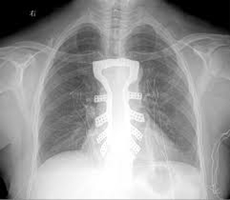

In the first operation of its kind in the world, a cancer patient has successfully been implanted with a 3D printed titanium sternum and rib implant.

The implant operation was carried out on a Spanish patient, 54, diagnosed with a chest wall sarcoma (a form of cancer in which a tumour grew inside or around the rib cage). The patient needed a part of the rib cage including the sternum to be removed.

The technology allowed for the creation of an implant that accurately replicated the size and form of the patient' rib cage.

For making the implant, the company created a 3-D model of the patient's chest wall and tumor, with the help of high-resolution CT scans. The same model was used by the surgical team to determine where to cut the patient's rib cage.

The printing of the implant was done at Lab 22, the 3-D printing lab of the Commonwealth Scientific and Industrial Research Organisation (CSIRO), Australia's national science agency. An electron beam is used in the printer to melt titanium powder into a 3-D object made with fine layers.